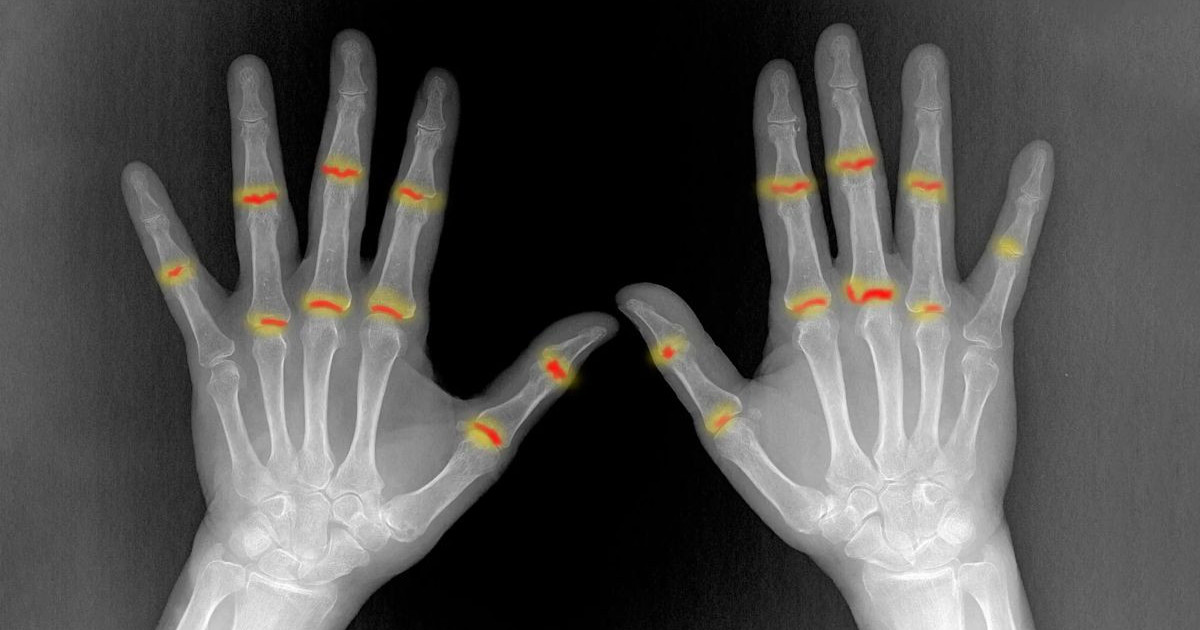

Για πολλά χρόνια η επιστημονική κοινότητα γνώριζε ότι η ψωρίαση δεν περιορίζεται μόνο στην επιφάνεια του δέρματος. Ένα σημαντικό ποσοστό ασθενών, περίπου το 30%, αναπτύσσει τελικά ψωριασική αρθρίτιδα, μια επώδυνη και συχνά μη αναστρέψιμη φλεγμονώδη πάθηση. Το ερώτημα που παρέμενε αναπάντητο, ωστόσο, ήταν το «γιατί». Γιατί ορισμένοι ασθενείς εμφανίζουν αρθρίτιδα ενώ άλλοι όχι; Και πώς ακριβώς μεταδίδεται η φλεγμονή από το δέρμα στις αρθρώσεις;

Στους ασθενείς που αναπτύσσουν ψωριασική αρθρίτιδα, αυτός ο μηχανισμός ασφαλείας καταρρέει. Οι ινοβλάστες παρουσιάζουν δυσλειτουργία και αδυνατούν να ελέγξουν τους εισβολείς. Ως αποτέλεσμα, τα μυελοειδή κύτταρα ενεργοποιούνται ανεξέλεγκτα, προκαλώντας τη φλεγμονώδη αντίδραση που οδηγεί σε πόνο και καταστροφή της άρθρωσης.